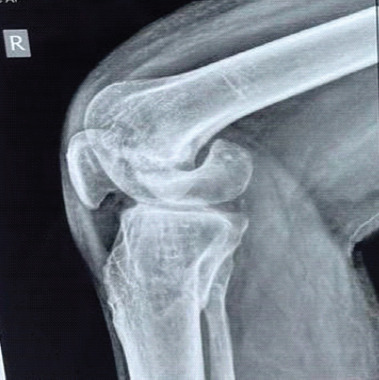

Case report: A case of a 38-year-old male who reported chronic right knee pain, swelling, and difficulty in ambulation due to a non-union Hoffa's fracture. Radiological findings indicated joint surface degeneration and instability. Given the chronicity and extent of articular damage, the patient underwent total knee arthroplasty (TKA) along with open reduction and internal fixation (ORIF) of the medial femoral condyle under spinal anesthesia. A posterior-stabilized knee system (Smith and Nephew, femur-5, tibia-5, polyethylene insert 13 mm) was implanted using Palacos bone cement. The patient recovered well and regained mobility with significant pain relief.